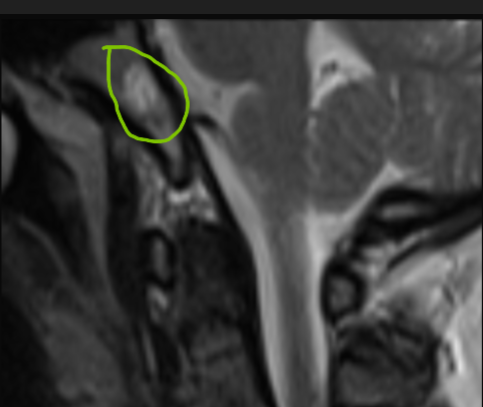

*Case Summary: 8 mm nodular lesion in the clivus, hyperintense on T1 and T2.

*Why Hyperintense on T1?

•High signal from vascular pools and fatty content

•T1 hyperintensity is a typical feature

*Why Hyperintense on T2?

•High water content and vascular channels → long T2 signal

•Bright, well-defined appearance on MRI